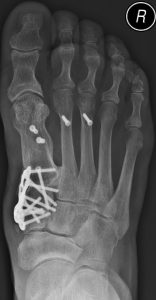

Update orthopädische Rheumatologie – Bis wann ist der Gelenkerhalt möglich?31. August 2022 Abb. 1: Zottige, hoch aktive Synovialitis im dorsomedialen Rezessus eines linken Kniegelenkes. (Bild: Gaulke) Die Entscheidung zwischen Erhalt, Ersatz, Resektion oder Versteifung eines Gelenkes bei entzündlich-rheumatischen Erkrankungen ist von vielen Faktoren abhängig und sollte von erfahrenen Rheumachirurgen vorgenommen werden. Im Folgenden gibt der Experte und derzeitige Präsident der Deutschen Gesellschaft für Orthopädische Rheumatologie (DGORh) eine Übersicht zu den aktuellen Optionen. Vor der Ära der Biologika war der Gelenkerhalt häufig nur durch eine totale Synovialektomie möglich. Bei noch intaktem Gelenk spricht man dabei von einer Frühsynovialektomie, liegen bereits Gelenkschäden vor, so wird die Prozedur als Spätsynovialektomie bezeichnet. Durch die Entfernung der Gelenkinnenhaut mit anschließender Radiosynoviorthese war es in vielen Fällen möglich, über Jahre die Gelenkzerstörung aufzuhalten oder zumindest zu verlangsamen und das Gelenk zu erhalten. Seit Einführung der Biologika (bDMARDs) und der small molecules (tsDMARDs) schreitet die Gelenkzerstörung sehr viel langsamer voran als unter den klassischen Basistherapeutika (csDMARDs). Das therapeutische Fenster für gelenkerhaltende Eingriffe ist somit länger geöffnet, was als günstig anzusehen ist. Dem entgegen steht allerdings, dass die Entzündung des Gelenkes unter wirksamer medikamentöser Therapie häufig schmerzarm oder -frei und daher vom Patienten unbemerkt verläuft, sodass sich das länger geöffnete therapeutische Fenster für gelenkerhaltende Eingriffe heute öfter ungenutzt schließt als früher, als die entzündeten Gelenke stark schmerzten (Abb. 1). Die Patienten entwickeln heutzutage häufig erst Beschwerden, wenn das Gelenk bereits stark zerstört ist und dann nur noch Resektionsarthroplastiken, Arthrodesen und Endoprothesen zur Schmerzbefreiung möglich sind. Um das primäre Ziel des Gelenkerhaltes zu erreichen, ist es daher unbedingt erforderlich, Hausärzte, internistische und orthopädische Rheumatologen sowie die Patienten selbst dafür zu sensibilisieren, sich bei persistierenden Gelenkschwellungen frühzeitig beim orthopädischen Rheumatologen vorzustellen, um durch eine zeitnahe Synovialektomie die Gelenke möglichst lange erhalten zu können. Da durch die bDMARD- und tsDMARD-Therapie die Entzündung häufig beruhigt oder stark reduziert werden kann, kommen für diese Patienten, vor allem an der unteren Extremität, auch achskorrigierende Osteotomien zur Anwendung, welche früher der Arthrose vorbehalten waren. Abb. 2: Klassische Vorfußkorrektur bei entzündlich-rheumatischen Erkrankungen: Tarsometatarsale I-Arthrodese und Resektionsarthroplastik Zehengrundgelenke II–V nach Hoffmann/Tillmann rechts. Abb. 3: Vorfußkorrektur analog zum Senk-Spreiz-Fuß bei beruhigter Krankheitsaktivität: Tarsometatarsale I-Arthrodese, Modifizierte Chevronosteotomie und Verkürzungsosteotomien MFK II und III rechts. Auch am Fuß haben die varisierende Osteotomie des Fersenbeins gegenüber der subtalaren Arthrodese und die Verkürzung der Mittelfußknochen bei Überlänge gegenüber den Resektionsarthroplastiken auch bei entzündlich-rheumatischen Erkrankungen an Bedeutung gewonnen. Die Resektionsarthroplastik der Zehengrundgelenke entspricht einer funktionellen Vorfußamputation, das heißt die Zehen sind zwar erhalten, können aber nicht kraftvoll bewegt werden (Abb. 2). Bei erhaltenen Gelenken hingegen ermöglicht die kräftige aktive Beugung der Zehen einen physiologischeren dynamischen Gang (Abb. 3). Wie lange ein Gelenkerhalt trotz bestehender Schäden möglich ist, hängt maßgeblich von der Belastung des Gelenkes ab, so tolerieren die Gelenke der oberen Extremitäten deutlich stärkere sekundäre Arthrosen als die belasteten Gelenke der unteren Extremitäten. Da im Rahmen einer totalen Synovialektomie immer auch eine Denervation des Gelenkes durch Resektion der in die Synovialis endenden Nerven erfolgt, können beispielsweise an der Schulter bei intakter Rotatorenmanschette auch dann noch Spätsynovialektomien sinnvoll durchgeführt werden, wenn die knöchernen Konturen des Humeruskopfes und des Glenoids, trotz des Verlustes des Knorpels, erhalten sind. Auch am Ellenbogengelenk kann trotz vollständigen Verlustes des Knorpels noch eine gute schmerzfreie Funktion in vielen Fällen wiederhergestellt werden. Insbesondere im Hinblick auf die relativ hohe Komplikationsrate der Ellenbogenendoprothesen sollten hier die Möglichkeiten der gelenkerhaltenden Eingriffe ausgeschöpft und die Indikation zur Endoprothese streng gestellt werden. Am Handgelenk kann bei geringer Krankheitsaktivität durch Sehnentransposition und Teilarthrodesen häufig eine Reposition und Stabilisierung des Karpus erzielt werden. Durch Vermeidung der totalen Arthrodese des Handgelenkes bleibt dem Patienten eine Restbeweglichkeit erhalten, welche vor allem für die Körperpflege sehr wertvoll ist. Aufgrund der geringen Haltbarkeit der Swanson-Spacer an den Fingergrundgelenken sollte auch hier bei beginnender Subluxation mit aktiv überwindbarer Schwanenhalsdeformität durch das Littler-Release mit Synovialektomie eine Stabilisierung der Fingergrundgelenke unter Gelenkerhalt durchgeführt werden. An den Mittelgelenken der Finger gestaltet sich aufgrund des kleinen Gelenkraumes und des engen Gelenkspaltes die totale Synovialektomie häufig schwierig. Neue Therapiekonzepte mit Oberflächenersatzprothesen an den Fingermittelgelenken kommen hier bei Kongruenzverlust durch stärkere knöcherne Arrosionen zunehmend zur Anwendung. An den Endgelenken ist die Synovialektomie ohne Versteifung in der Regel nicht erfolgversprechend. Am Unterarm kann auch bei entknorpelten Gelenkflächen ein Erhalt des Radius- und Ulnaköpfchens bei geringer Krankheitsaktivität zunehmend angestrebt werden. Dies verhindert die Instabilität der Aufhängung des Radius an der Elle, da die Membrana interossea gespannt bleibt. An der unteren Extremität toleriert das Hüftgelenk die Destruktion am geringsten. Synovialektomien an der Hüfte können arthroskopisch durchgeführt werden. Bei stärkeren Destruktionen sollte jedoch großzügig der endoprothetische Ersatz erfolgen. Am Kniegelenk kann bei Achsfehlstellung durch eine Korrektur der Achse der asymmetrische mechanische Reiz vom Gelenk genommen werden. Diese sollte aber immer dann, wenn eine Synovialitis vorliegt, mit einer totalen Synovialektomie kombiniert werden. Am oberen Sprunggelenk wird die arthroskopische Synovialektomie häufig mit einer Resektion von Osteophyten kombiniert, welche die Dorsalextension einschränkten. Solange der Talus nicht in das Pilon tibiale einbricht, kann auch hier der Versuch des Gelenkerhaltes unternommen werden. Bei einer Instabilität des Subtalargelenkes sollte sehr genau abgewogen werden, ob eine varisierende Verschiebeosteotomie des Kalkaneus zu einer ausreichenden Stabilisierung führt. Ansonsten sollte hier der subtalaren Arthrodese der Vorzug gegeben werden. Im Großzehengrundgelenk kann eine Synovialektomie mit Cheilektomie zu guten Ergebnissen führen, wenn die Grunderkrankung ausreichend beherrscht ist. An den MTP II–V kommt der plantaren Bursitis, welche das plantare Fettgewebe zerstört, eine größere Bedeutung als der Arthritis des Gelenkes zu. Hier sollte eine Verkürzungsosteotomie der Mittelfußknochen unter Erhalt der Gelenke nur dann durchgeführt werden, wenn die Grunderkrankung durch die Immunsuppression ausreichend beherrscht ist und keine plantaren Bursitiden vorliegen. Eine Synovialektomie an den Zehengrundgelenken ohne Resektion der plantaren Bursae ist in der Regel nicht zielführend, da mit einem frühen Rezidiv zu rechnen ist. Fazit Zusammenfassend bestehen unter guter Krankheitsberuhigung zunehmend auch für extraartikuläre Korrekturen gute Indikationen. Bei hoher entzündlich-rheumatischer Krankheitsaktivität hingegen werden mit den klassischen Gelenkoperationen bessere Ergebnisse erzielt. Zwischen diesen Optionen abzuwägen bedarf großer Erfahrung, weshalb die Behandlung in einem Spezialzentrum für operative Rheumachirurgie empfohlen wird. Eine Liste dieser Kliniken finden Sie unter www.dgorh.de Autor: Prof. Dr. med. Ralph GaulkeUnfallchirurgische Klinik, Sektion Obere Extremität, Fuß- und Rheumachirurgie Medizinische Hochschule HannoverCarl-Neuberg-Str. 1, 30625 Hannover